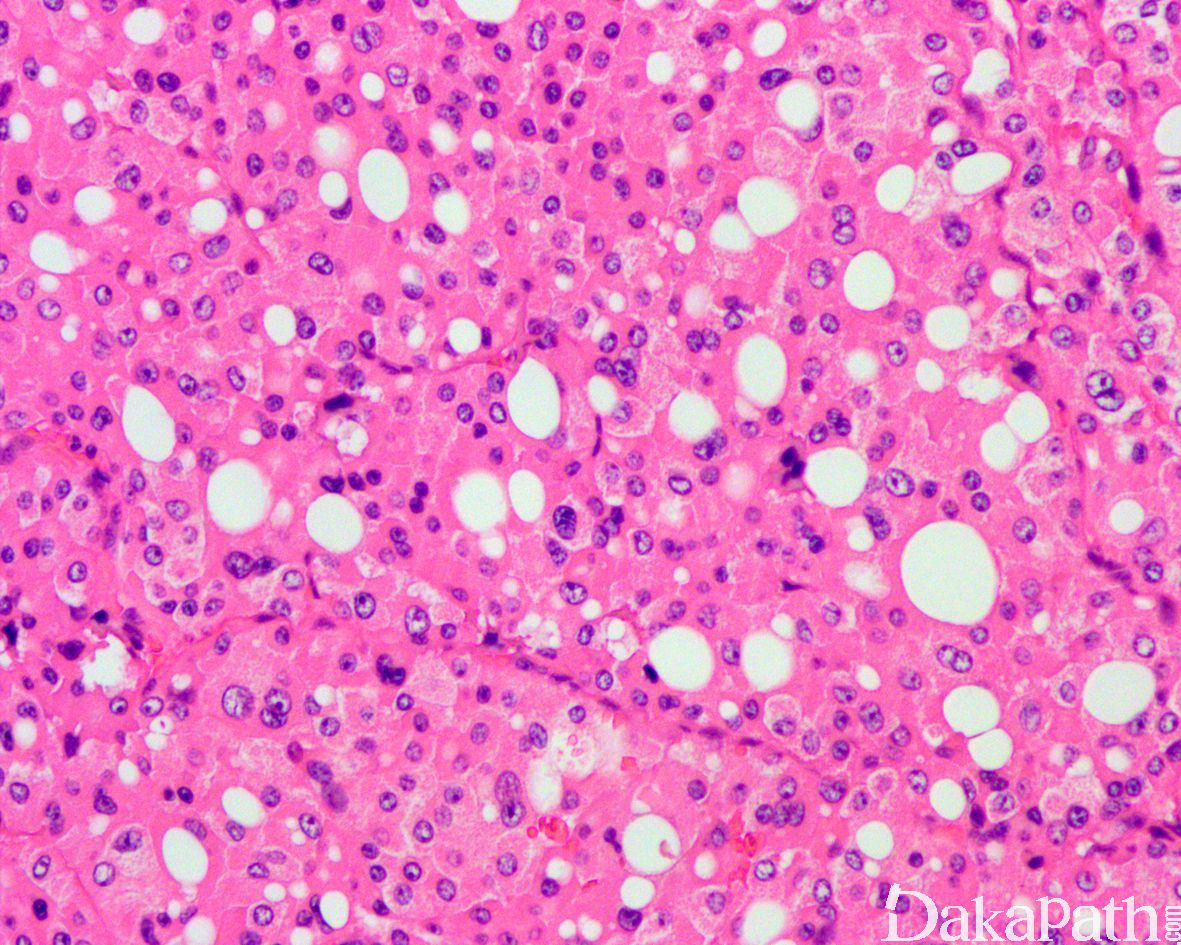

组织学特征不能归类为特定的肾细胞癌类型,该类型包括但不限于:

1)具有两种或两种以上特指类型的肾细胞癌组织形态,伴黏液产生或伴不能识别的上皮细胞类型;

透明细胞癌样肾细胞癌伴有明显的平滑肌间质;

常见血管淋巴管浸润及坏死